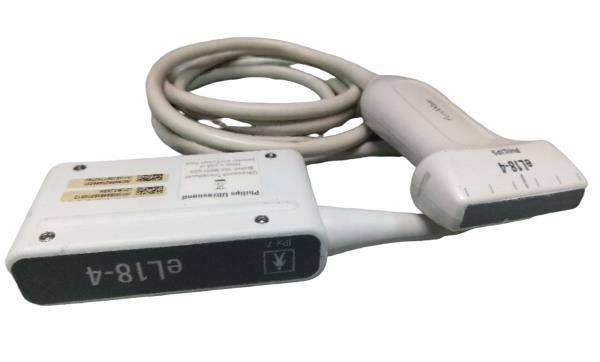

The CE Digital Laptop Ultrasound Scanner is designed to provide high-quality imaging for medical professionals. With its advanced 7.5MHz linear probe, this scanner captures clear and precise images, allowing for accurate diagnostics. It is especially beneficial for procedures requiring detailed visualization, such as vascular and musculoskeletal examinations. This tool empowers healthcare providers, so they can deliver better patient care through enhanced imaging technology.